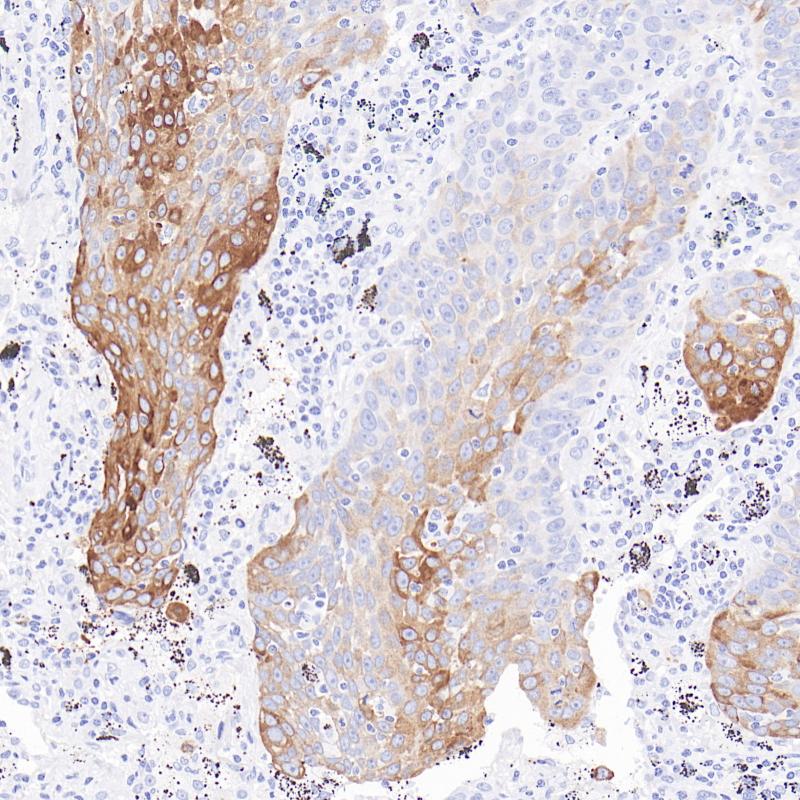

肝细胞(Hepatocyte)是肝脏的主要功能细胞,占肝脏细胞总数的80%。Hepatocyte又称Hep Par-1,是肝组织及肝细胞肿瘤的特异性标记物。在临床病理诊断中,Hepatocyte的特征和表达模式对于肝脏疾病的诊断、分类和预后评估具有重要意义。

阳性对照

肝细胞癌

亚细胞定位